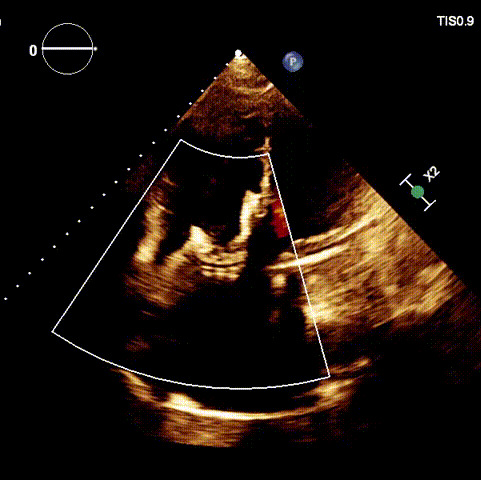

術(shù)后超聲

近日,廈門大學(xué)心血管病醫(yī)院王焱教授帶領(lǐng)的結(jié)構(gòu)性心臟病團(tuán)隊(duì),成功應(yīng)用LuX-Valve Plus經(jīng)血管三尖瓣置換系統(tǒng),為一例高危三尖瓣重度反流患者開展經(jīng)血管三尖瓣置換手術(shù)。此次手術(shù)系LuX-Valve Plus人工瓣膜在福建省的首例植入,手術(shù)過程順利,術(shù)后患者三尖瓣反流顯著改善,標(biāo)志著由葛均波院士團(tuán)隊(duì)作為主要研究者的LuX-Valve Plus經(jīng)血管三尖瓣置換系統(tǒng)全國多中心臨床研究的再一次成功實(shí)踐,為三尖瓣介入治療的醫(yī)學(xué)循證打下了夯實(shí)的基礎(chǔ)。 、